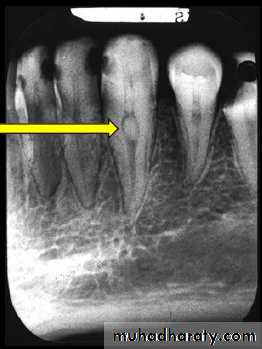

Radiographic Features

• Radiolucency at root and adjacent bone• Irregular shortening or thinning of root

• Loss of Lamina dura.